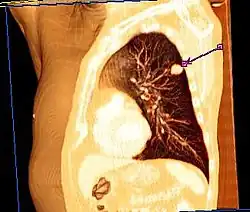

Eine wichtige Rolle bei der Diagnose eines Bronchialkarzinoms spielen die bildgebenden Verfahren. So sind das Röntgen des Thorax in zwei Ebenen und die Computertomografie (CT) des Thorax die Mittel der Wahl zum Erkennen und Lokalisieren von Bronchialkarzinomen. Die Positronen-Emissions-Tomographie (PET) kann darüber hinaus zum Aufspüren von Fernmetastasen verwendet werden. Die Bronchoskopie wird zur Gewinnung von Gewebeproben für die histologische Beurteilung des Tumors herangezogen. In der Labordiagnostik können die Tumormarker Neuronenspezifische Enolase (NSE) und CYFRA 21-1 zur Diagnosestellung mitverwendet werden, die Ergebnisse sind aber nicht sicher.